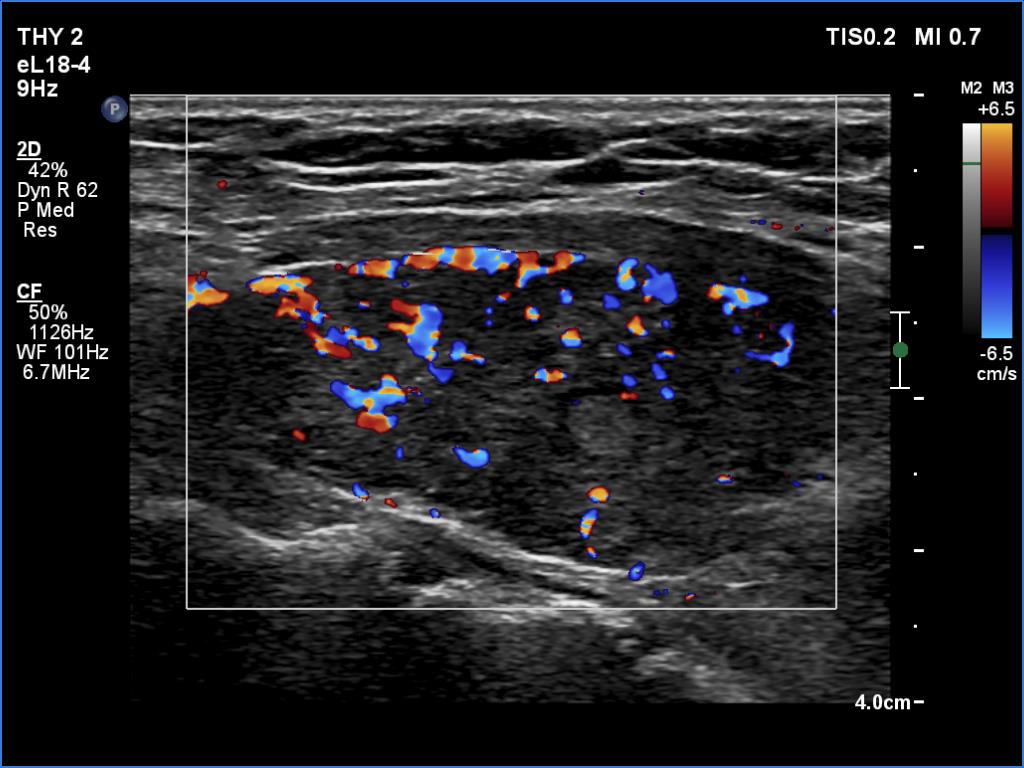

Left lobe, longitudinal view, color Doppler mode. The vascularity is slightly increased.